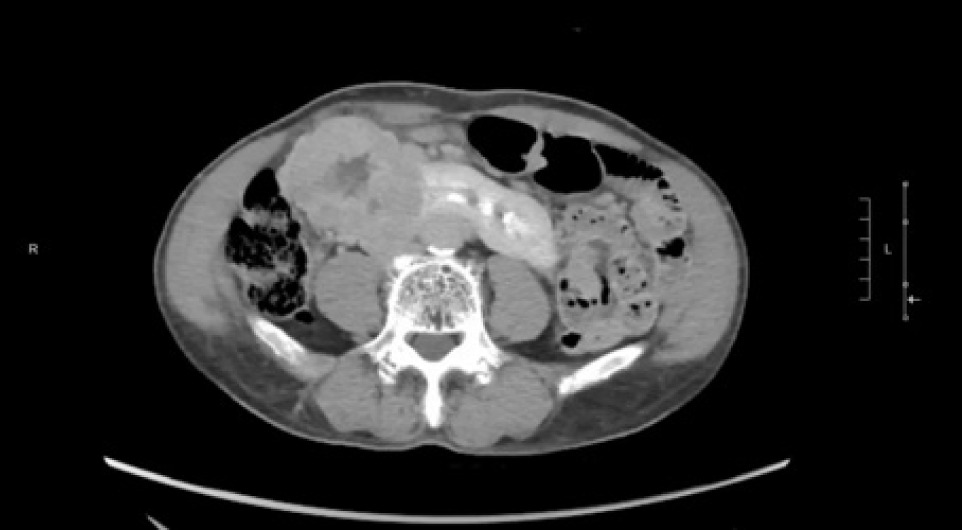

A 74-year-old Chinese male patient, ex-smoker, and social drinker, with a history of carcinoma of prostate in remission with laparoscopic radical prostatectomy done 11 years ago presented with an incidental finding of a right abdominal mass without frank symptoms. Preoperative eGFR ranges from 80 to 90 mL/min/1.73m2. Computed tomography (CT) showed a 7 cm heterogeneous mass on the right side of the HSK with complex hilar anatomy (Figures 1 & 2). Dual tracer (C-11 acetate and F18 FDG) positron emission tomography (PET-CT) showed moderate and mildly avid renal cell carcinoma (RCC) arising from HSK, without nodal or distant metastases. A 3D image reconstruction using FUJIFILM Synapse system was performed, showing complex tumor and vascular anatomy (two renal arteries and an additional artery to isthmus) (Figure 3). An open partial right nephrectomy was planned.

Figure 1: Axial cut of arterial phase-enhanced CT abdomen at the tumor level.

Figure 2: Axial cut of delayed phase-enhanced CT abdomen at the tumor level.